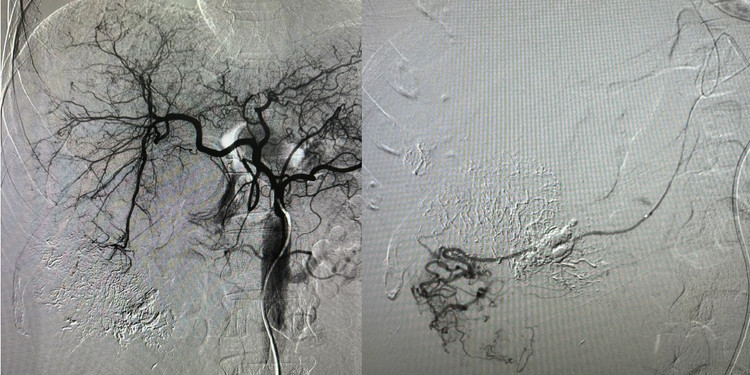

Can thiệp nút mạch gan - Ảnh BVCC

Trong các trường hợp này, phương pháp điều trị hiệu quả được ưu tiên là kỹ thuật chụp và nút mạch gan. Bằng việc sử dụng hệ thống chụp mạch số hóa xóa nền (DSA), các bác sĩ sẽ đưa một ống thông có kích thước rất nhỏ vào hệ thống mạch máu để tiếp cận vị trí đang chảy máu.

Tại đây, chất gây tắc mạch sẽ được bơm vào nhằm làm tắc hoàn toàn mạch máu bị tổn thương, giúp cầm máu nhanh chóng, hạn chế biến chứng và tăng cơ hội sống sót cho người bệnh.